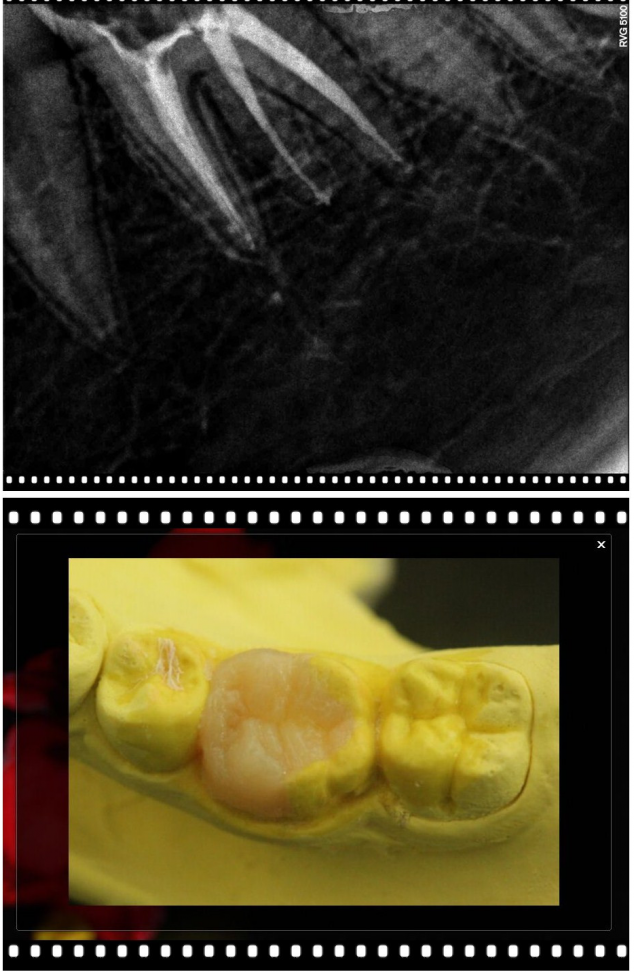

以下病例大部分是以Kerr的低端Neofil通用樹脂修復(fù)(基本都是粗拋紅標(biāo)車針),修復(fù)調(diào)合后即刻照。